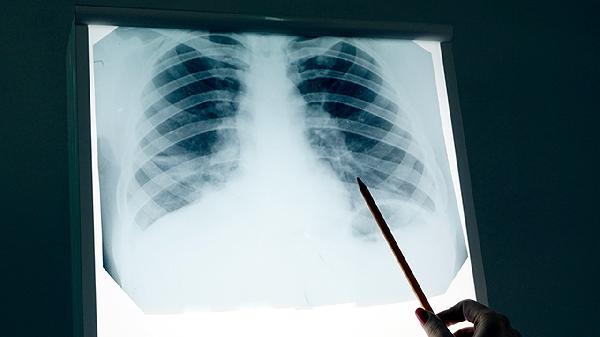

周围型肺癌最常见的组织类型有哪些

周围型肺癌最常见的组织类型有腺癌、鳞状细胞癌、大细胞癌、腺鳞癌和类癌。腺癌占比最高,多见于肺外周部位;鳞状细胞癌多与吸烟相关;大细胞癌恶性程度较高;腺鳞癌兼具两种成分;类癌生长相对缓慢。